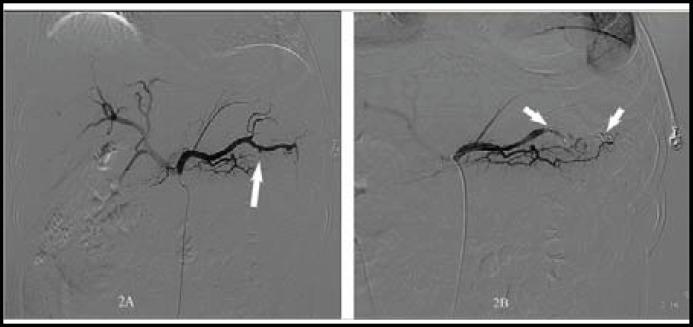

Rupture of splenic artery aneurysm remains an uncommon cause of hypovolemic shock although it is the third most common intra-abdominal aneurysms. It is difficult to diagnosis timely and entails a significant morbidity and mortality. We present three uncommon cases of bleeding from upper gastrointestinal tract as a result of rupture of splenic artery aneurysm to stomach in patients with liver cirrhosis or infectious endocarditis. We also reviewed the literature and these case reports highlighted that rapid resuscitation, diagnostic imaging, surgical consultation, and alternatively transarterial embolization were the priorities in the management. Early diagnosis and intervention for ruptured splenic artery aneurysm are crucial for patient's survival; therefore, it must be kept in mind as feasible etiology of life-threatening gastrointestinal bleeding, especially in patients with underlying liver cirrhosis or infective endocarditis.

脾动脉瘤破裂虽然是引起低血容量性休克的第三大常见腹腔内动脉瘤,但仍是一种罕见的原因。它很难及时诊断,导致发病率和死亡率显著增加。我们报告了 3 例因肝硬化或感染性心内膜炎导致胃脾动脉瘤破裂出血至上消化道的罕见病例。我们还回顾了文献,这些病例报告强调了快速复苏、诊断成像、外科咨询和选择性经动脉栓塞是治疗的重点。脾动脉瘤破裂的早期诊断和干预对患者的生存至关重要;因此,对于危及生命的胃肠道出血,特别是在有基础肝硬化或感染性心内膜炎的患者,应将其视为可能的病因。